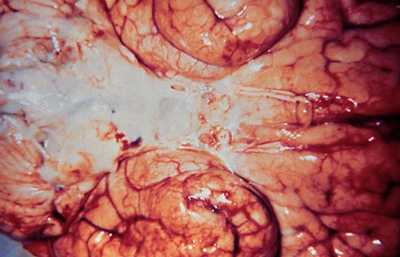

| Мозг при менингите, вызванном Haemophilus influenzae |

По данным крупных исследований, на долю бактерий группы НAСЕК приходится 1% случаев инфекционного эндокардита (преобладают Haemophilus spp. ). Вызванный ими эндокардит обычно имеет подострое течение и нередко осложняется септической эмболией . Эмболия крупных артерий встречается в среднем у 28% больных, но в некоторых наблюдениях эта цифра достигает 60%. У 33% больных эндокардит естественных клапанов , вызываемый Haemophilus spp. , возникает на фоне уже имеющихся пороков сердца , 60% обращаются к врачу менее чем через 2 мес от начала заболевания, у 50% к моменту первого осмотра имеется анемия . У 19% больных развивается сердечная недостаточность . Летальность составляет 30%, причем большинство больных умирают от эмболии сосудов головного мозга .